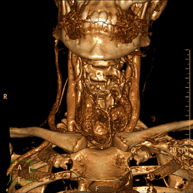

Prova radiològica que consisteix en obtenir imatges de l'os penyal del temporal (oïda interna, mitjana i externa) d'alta definició anatòmica, mitjançant l'ús d'un equip de TC (Tomografia Computeritzada). Indicacions: pèrdua d'audició sobtada o crònica, quadres vertiginosos, mareig, malformacions congènites. - Angio-TC Troncs Supraaòrtics

Prova radiològica que consisteix en obtenir imatges de les artèries caròtides del coll d'alta definició anatòmica, mitjançant l'ús d'un equip de TC (Tomografia Computeritzada) i la injecció de contrast intravenós. Posteriorment, les imatges són reconstruïdes en tres dimensions (3D). Indicacions: accident vascular cerebral agut, accident vascular transitori, buf cardíac. - TC Columna cervical